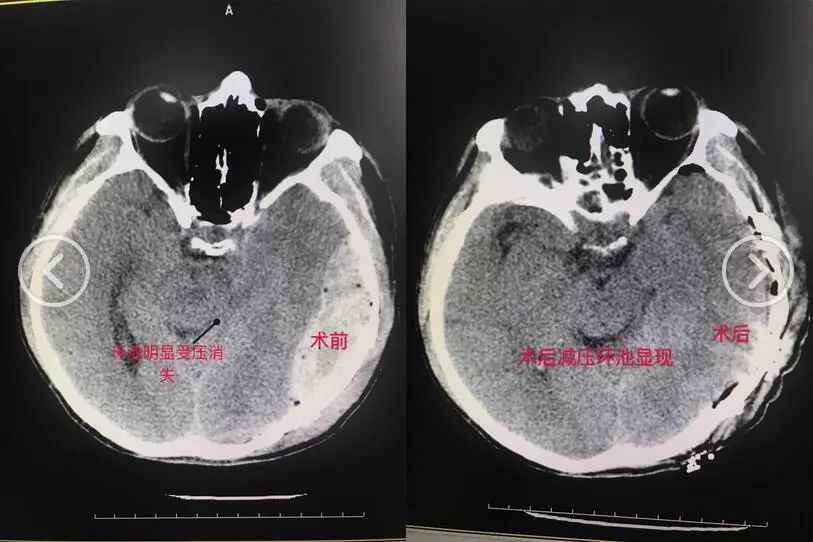

比如我们改良传统的“脑出血”去骨瓣减压颅内血肿清除术,在术前术中做好充分的评估,尽可能做到小骨窗微创清除、一期还纳骨瓣,免去了原来需要行二期颅骨修补的必要,最大程度较少患者的损伤和经济压力。